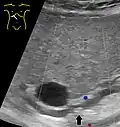

Abdominal ultrasonography of a common bile duct stone -

Choledocholithiasis (stones in common bile duct) is one of the complications of cholelithiasis (gallstones), so the initial step is to confirm the diagnosis of cholelithiasis. Patients with cholelithiasis typically present with pain in the right-upper quadrant of the abdomen with the associated symptoms of nausea and vomiting, especially after a fatty meal. The physician can confirm the diagnosis of cholelithiasis with an abdominal ultrasound that shows the ultrasonic shadows of the stones in the gallbladder.